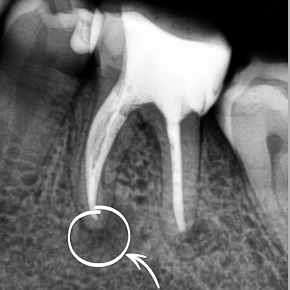

Нужно ли извлекать сломанный инструмент в корневом канале?